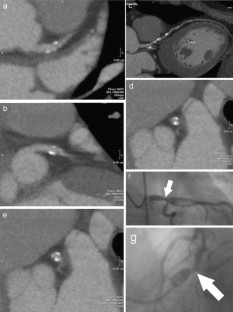

Fig. 3